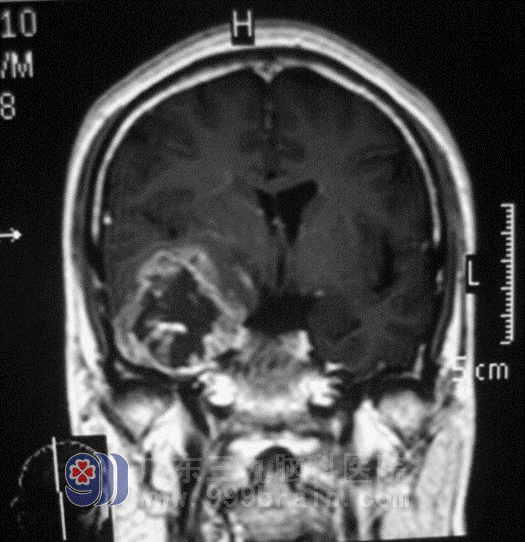

Mr. Liu, 54-year-old, was too busy with his business to get a cold. A week ago, he had a dizzy without any reasons, his son and son-in-law thought he was too tired in career, so he had a rest at home for a week but didn’t have any improvement, he went to a hospital to check brain CT, the result showed: cerebellum interspace. His whole family didn’t believe the result. Then his son found GuangDong 999 Brain Hospital on the Internet and connected Lu Ming Director of the Fifth Section of the Department of Neurosurgery. After checking on brain MR, Lu Ming Director found his brain textures were pressured obviously and diagnosed him as right lobus temporalis interspace, that is, malignant glioma.

Within complete checking before operation, on May 19, Lu Ming Director carried out the operation that he cut off right lobus temporalis for Mr. Liu. Lu Ming Director dealt with the operation steadily and completed the hard operation successfully. Mr. Liu entered recovery stage smoothly, by being in the hospital to treat, Mr. Liu had not any other diseases to happen and he turned to Radiotherapy Department for further treatment.

before operation